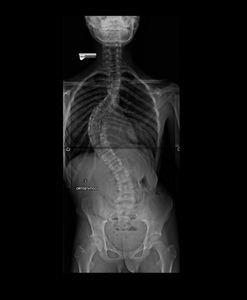

Há um ano, sua mãe reparou que ele começou a andar torto e comentou a situação comigo, Adriana, com quem ela trabalha ocasionalmente. Ofereci de levarmos o menino a um ortopedista particular e assim foi. Na consulta, o médico realizou exames de imagem (anexos a essa campanha) e, chocado, diagnosticou Juan com uma escoliose gravíssima, recomendando cirurgia em caráter de urgência.

De 1 ano para cá, desde o diagnóstico, a angulação da coluna de Juan tem piorado, apesar do uso do colete e do tratamento em sessões de RPG, e a cirurgia é inavitável.

Além da preocupação natural da família com o quadro geral, o grande receio é de que a coluna venha a comprometer o seu pulmão, já que Juan tem asma desde muito novo. Por isso, em razão da urgência e evolução gradativa do quadro, lançamos essa campanha! O valor arrecado será integralmente destinado à cirurgia e ao tratamento da escoliose de Juan.